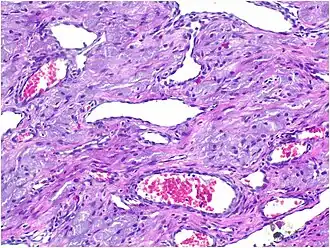

Histopathological Characteristics

Histopathologically, congenital epulis is usually characterized by the presence of big, rounded cells that fill the mucosa's lamina propria and have round to oval nuclei and an abundance of eosinophilic cytoplasm.[10] A thin layer of connective tissue separated the surface layer of cells from the growing new cells. Numerous histological traits, such as a fibrous and granulomatous appearance, have been reported in recent research.[10]

Microscopically, congenital epulis is composed of:

- Sheets of proliferating polygonal to round cells with overlying thin squamous, eosinophilic, granular cytoplasm[12][13]

- Centrally located, round nuclei [7]

These histopathological features are essential in distinguishing congenital epulis from other gingival and soft tissue neoplasms.

Infantile Myofibroma

Infantile myofibroma is a benign fibrous tumor that may present as a gingival mass in newborns.[6] However, histologically, it is composed of fibrous tissue rather than granular cells, distinguishing it from congenital epulis.[13]